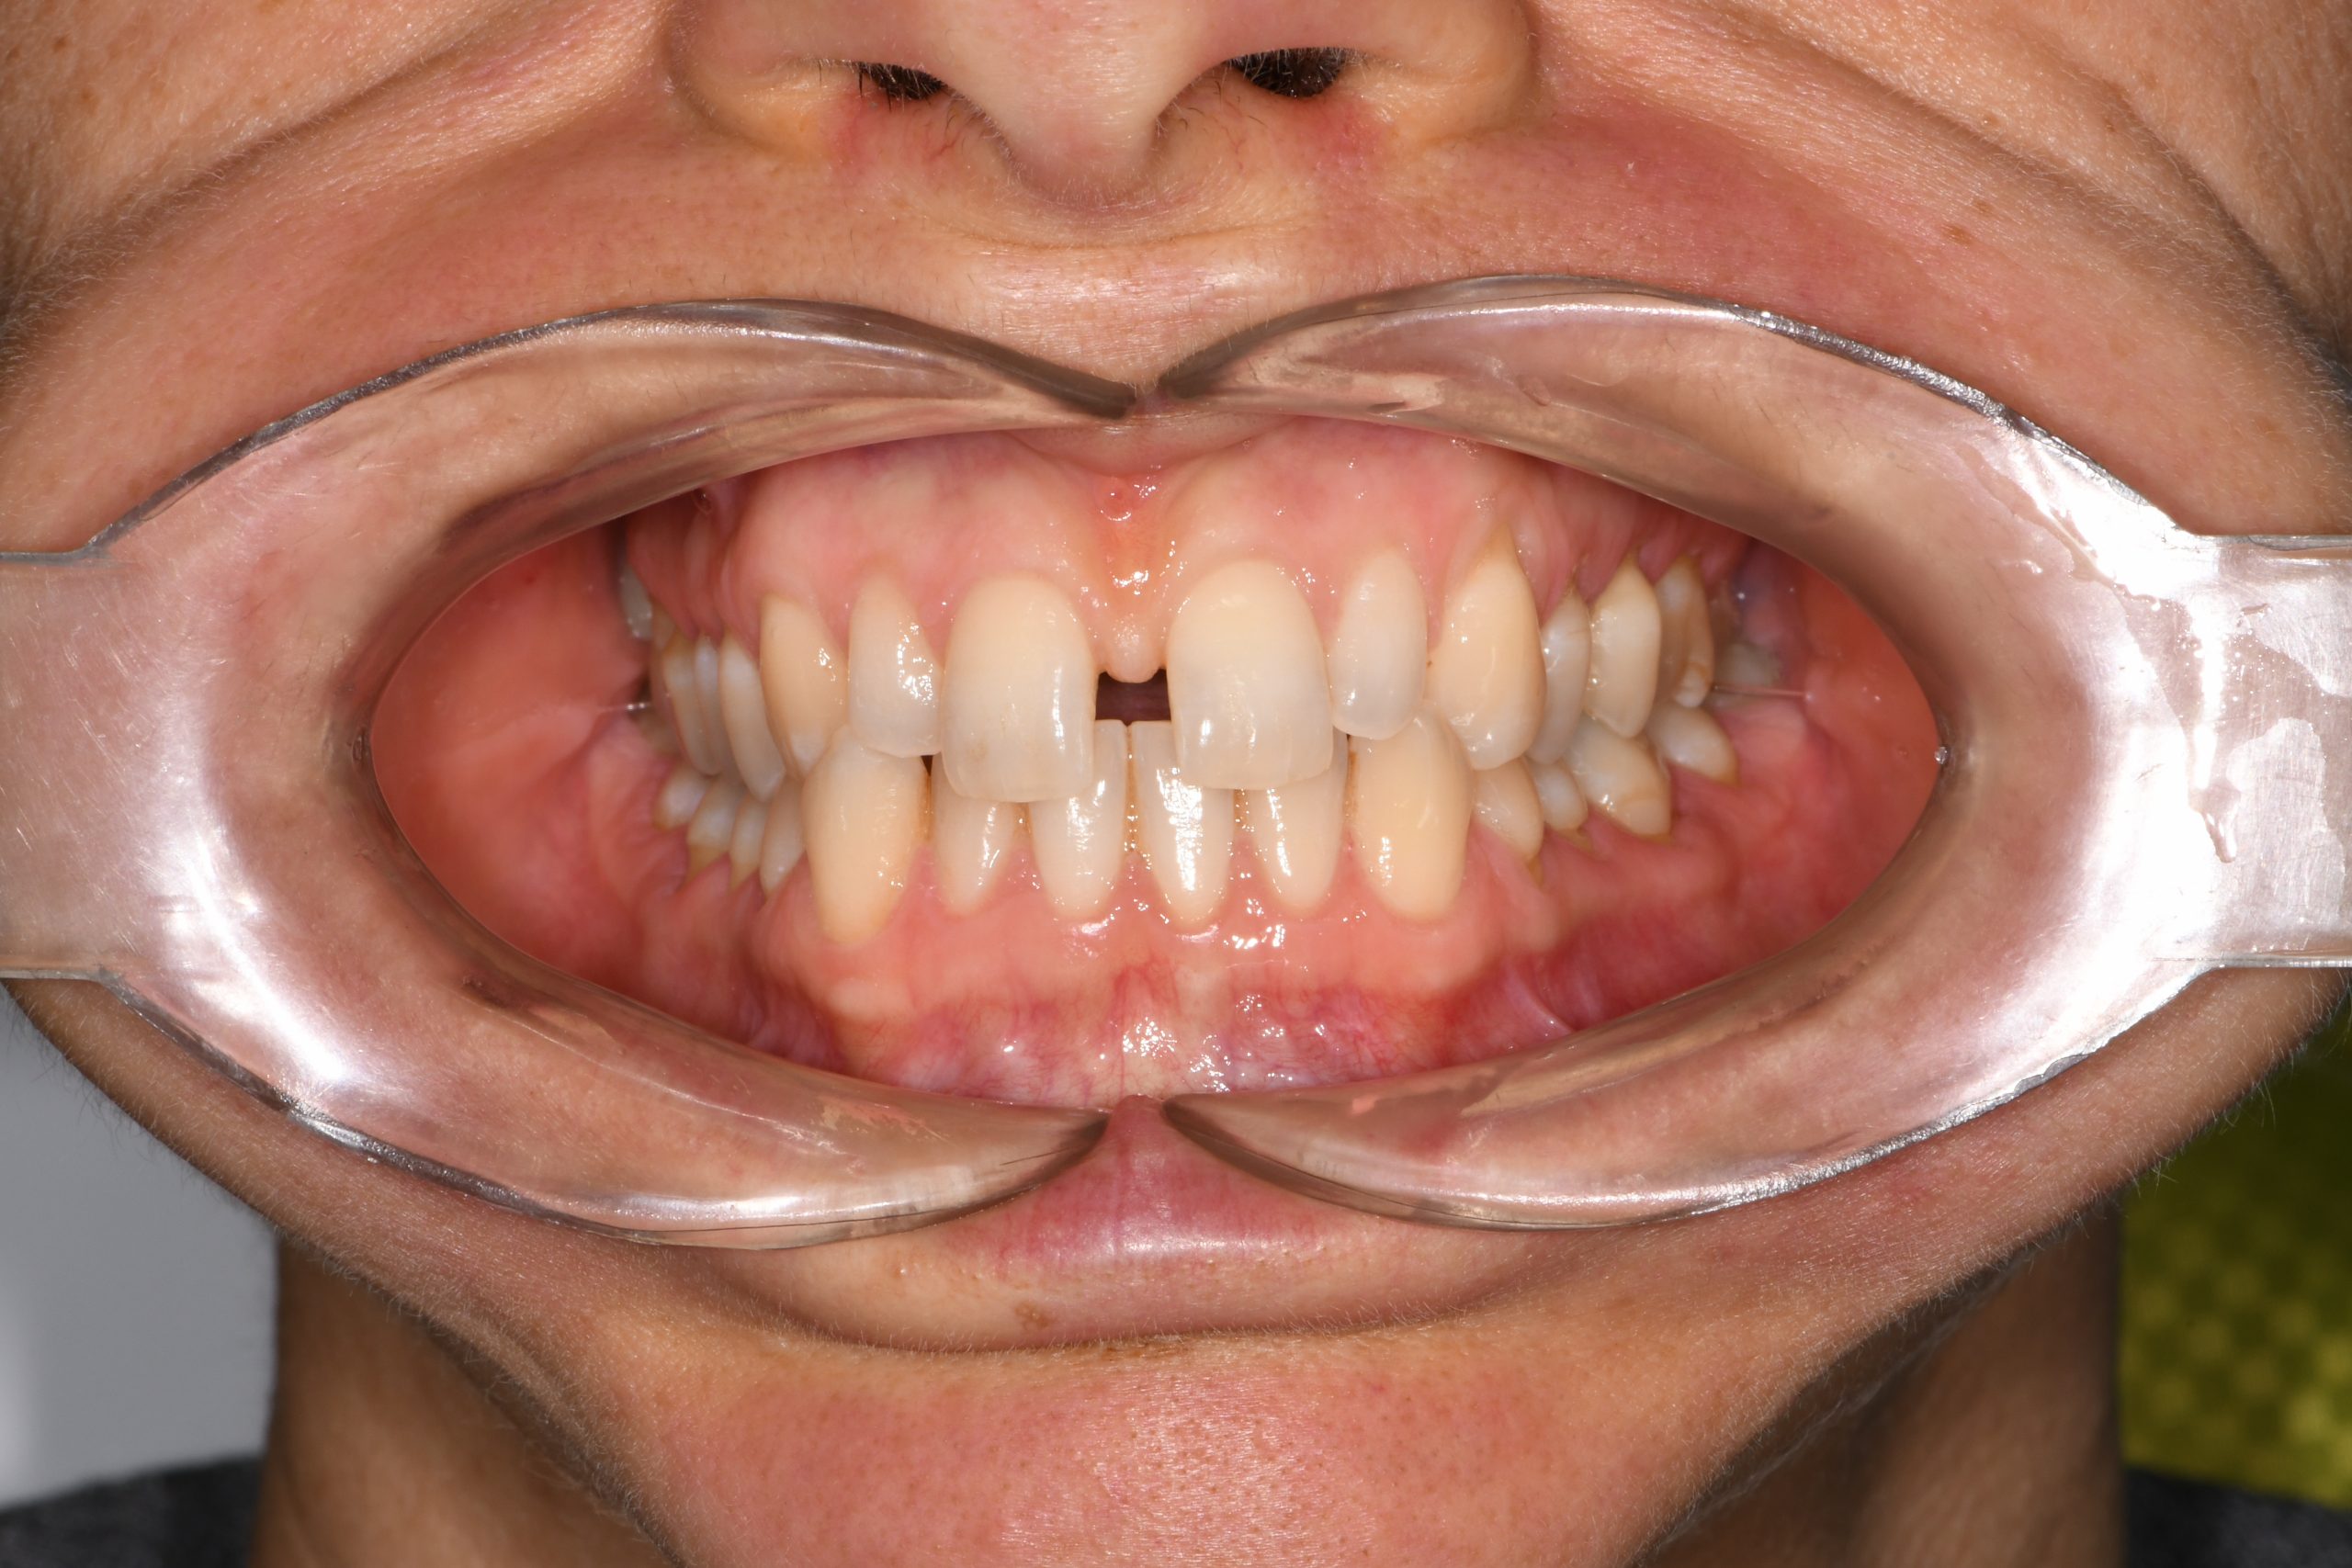

Az elmúlt évekből rengeteg szakmai referenciát tudnánk bemutatni, amelyek különböző fogszabályozási problémákat oldottak meg. Válogatva a több száz esetből, ezen az oldalon olyan képeket, információkat igyekeztünk bemutatni, amelyeknek a segítségével a jövőbeni pácienseinknek azt tudjuk üzenni: A Te fogsorod is lehet gyönyörű!

(Képeket a Pácienseink külön írásos beleegyezésével mutatjuk be!)